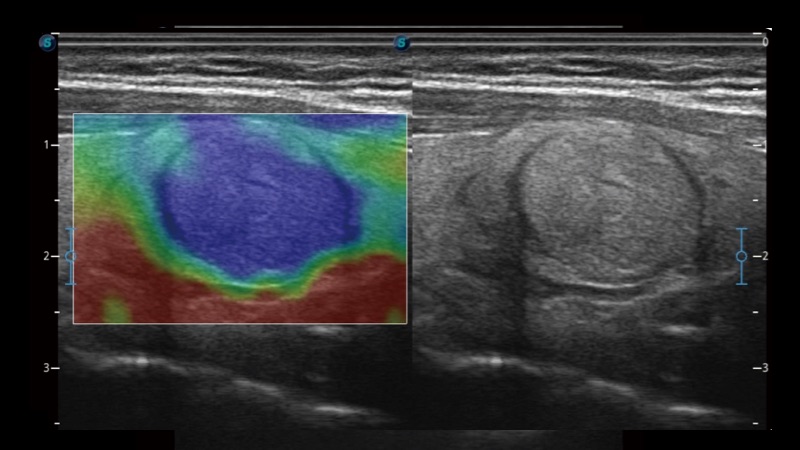

開(kāi)立醫(yī)療通過(guò)不斷的技術(shù)創(chuàng)新,為大眾的生命健康提供持續(xù)關(guān)愛(ài)。P12 Plus采用全新一代超聲成像平臺(tái),新平臺(tái)旨在將真實(shí)還原組織解剖結(jié)構(gòu)作為首要目標(biāo)。平臺(tái)采用全新集成化硬件模塊,搭載新一代芯片,系統(tǒng)性能得到大幅提升,為您的診斷提供了豐富的臨床信息。優(yōu)異的圖像表現(xiàn),豐富的探頭配置,全面的應(yīng)用功能,為您日常診斷提供了可靠的助手。

彩色多普勒超聲診斷系統(tǒng)